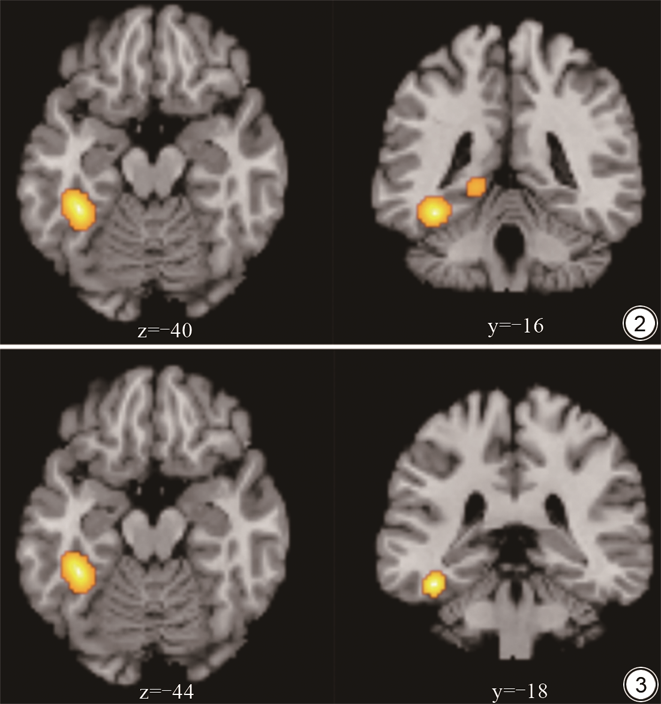

结合ReHo及ALFF/fALFF/dALFF数据元分析结果显示,PI患者相对于HCs左侧梭状回和海马旁回活动增高(见表2、图2),并未发现活动减低的脑区。分别对ReHo及ALFF/fALFF方法进行单独元分析:ALFF数据元分析结果显示,PI患者相对于HCs左侧梭状回活动增高(见表2、图3),并未发现活动减低的脑区;ReHo数据元分析结果显示,PI患者相对于HCs并未出现任何活动增高或减低的脑区。

| ReHo及ALFF/fALFF/dALFF | L | 梭状回 | 37/20 | -40 | -40 | -16 | 0.462 | 0.921 | 3640 |

| L | 海马旁回 | 30/27 | -18 | -38 | -2 | 0.381 | 0.277 | 928 | |

| ALFF | L | 梭状回 | 20/37 | -44 | -34 | -18 | 0.356 | 2.440 | 1360 |

注:PI:原发性失眠;HCs:健康对照组;ALE:激活似然估计法;ReHo:局部一致性;ALFF:低频振幅;fALFF:比率低频振幅;dALFF:动态低频振幅;BA分区:Brodmann分区;MNI:蒙特利尔神经病学研究所。